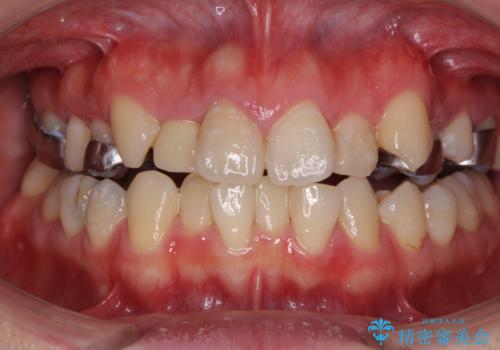

- 上下のデコボコと奥歯の咬みにくさを気にして来院された患者様です。

上顎骨の幅が下顎骨よりも小さいので、拡大装置により骨幅を広げて上下関係を改善し、その後インビザラインにて歯並びを整えることとしました。

上下の骨幅を改善したことで、スムーズに歯列矯正を行うことができました。

奥歯の咬み合わせを改善する必要があったため、治療は長期化しましたが、きっちりと仕上げることができました。